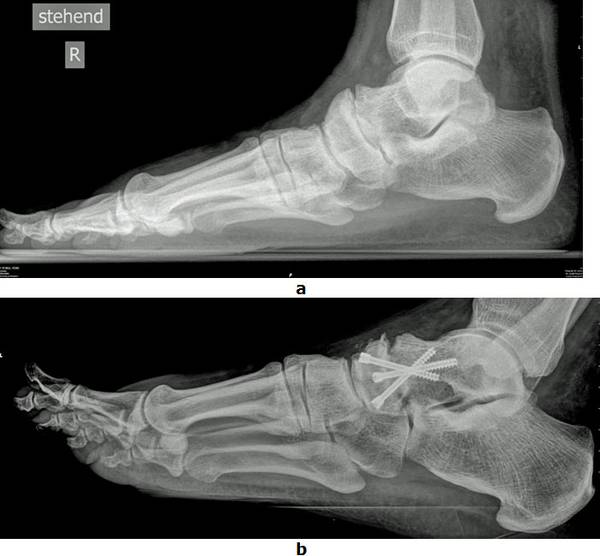

Abb.2: a Schmerzhafte isolierte Arthrose eines Mittelfußgelenkes (Talonaviculargelenk) mit Knochenanbauten. Trotz orthopädischer Schuhe war ein schmerzfreies Laufen nicht mehr möglich

b Isolierte Fusion des kaputten Gelenkes mit 3 Schrauben. Nach der Operation konnte der Patient wieder ohne Hilfsmittel Gehen.